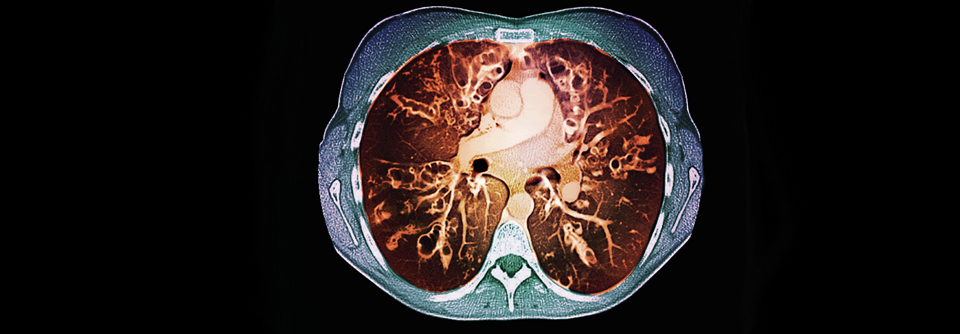

In der Behandlung von Patienten mit zystischer Fibrose ließen sich durch CFTR-Potenziatoren sowie CFTR-Korrektoren bereits große Fortschritte erzielen. In der Behandlung von Patienten mit zystischer Fibrose ließen sich durch CFTR-Potenziatoren sowie CFTR-Korrektoren bereits große Fortschritte erzielen. © Science Photo Library/St. Bartholomew‘s Hospital